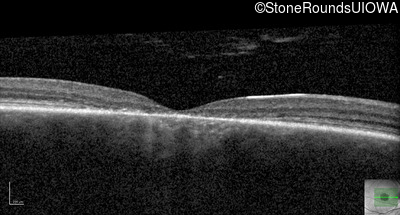

Infrared Fundus Photograph - Right - 20/125 -1

Exemplar